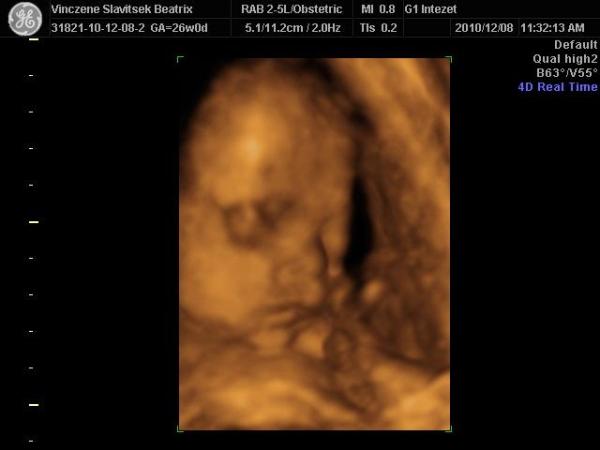

Voltam 4D uh-n a G1-ben és képzeljétek, készült kép is, bár eléggé bújócskázott a lepénybe, meg a köldökzsinór az arca előtt volt, úgy hogy eléggé betakart, de azért készült jó kép. Még mindig Kislány!!!

És mehetek újra uh-ra és most nem kellett fizetnem, mert rossz lett a gép, és nem írta ki dvd-re a vizsgálati filmet. Úgyhogy majd felhívnak h mikor menjek újra vizsgálatra és akkor kell majd fizetni, szóval tökre örültem, h 2vizsgálatom lesz 1 áráért! 8) :lol: :lol: Bár azt mondták akkor csak filmet kapok de ha lesz jó kép, majd kikönyörgök egyet!! A mérete alapján 27 hetesnek felel meg, szóval 1 héttel nagyobb, a súlya 957gramm, hossza 26cm!